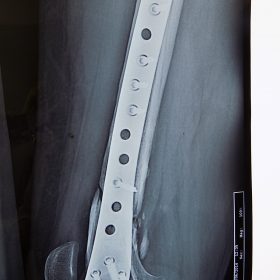

Τα κατάγματα της Διάφυσης των οστών της κνήμης και του Μηριαίου οστού στη σύγχρονη ΟΡΘΡΟΠΑΙΔΙΚΗ αντιμετωπίζονται με ΕΝΔΟΜΥΕΛΙΚΗ ΗΛΩΣΗ.

Δύο τομές 3 εκατοστών και 1 εκατοστού αντιστοίχως για την εισαγωγή και το κλείδωμα του ήλου μέσα στο οστό. Η μέθοδος είναι κλειστή,σχεδόν αναίμακτη,διάρκειας 60 λεπτών,με τη βοήθεια C-ARM (τηλεόρασης).

Στον ασθενή παρέχεται οπτικό υλικό (όλα τα χειρουργικά στάδια) σε CD ή Στικάκι,λόγω της δυνατότητας καταγραφής του χειρουργείου από το C-ARM Ο ασθενής περπατάει άμεσα μετεγχειρητικά στις 5 ώρες μετά την επέμβαση και εξέρχεται από το νοσοκομείο σε 1 -2 ημέρες.

Ο ασθενής επανέρχεται σε εργασία γραφείου εντός 15 ημερών και σε πιο βαριά χειρωνακτική εργασία εντός μηνός.